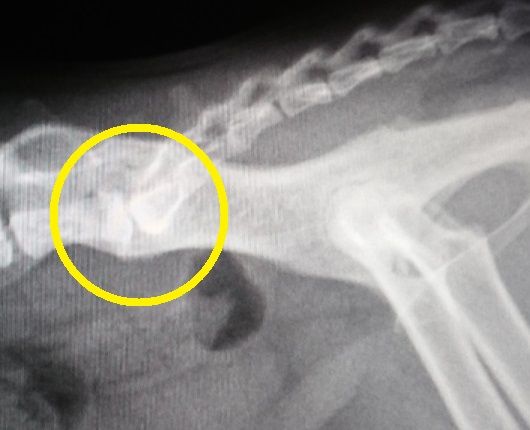

原因の一つが、こちら。

2012年:7歳のレントゲン

2014年:9際のレントゲン

2015年:10歳のレントゲン

2016年:11歳のレントゲン

2018年、本日、もう直ぐ13歳のレントゲン

背骨と尻尾の付け根の骨の状態の経過を年を追って見てみると、若い頃は、骨と骨の隙間もしっかり開いてましたが、2015年のレントゲンでは、先ずは、隙間がかなり狭くなって来ており、更に、2016年のレントゲンでは、骨の下の部分に突起が、これを我が家ではトケトケと呼んでいます。

実は、 2015年3月7日のブログ ​で、この状況の予兆を記載していました。

本日のレントゲンでは、隙間が無くなり、トケトケもかなり飛び出て来ています。